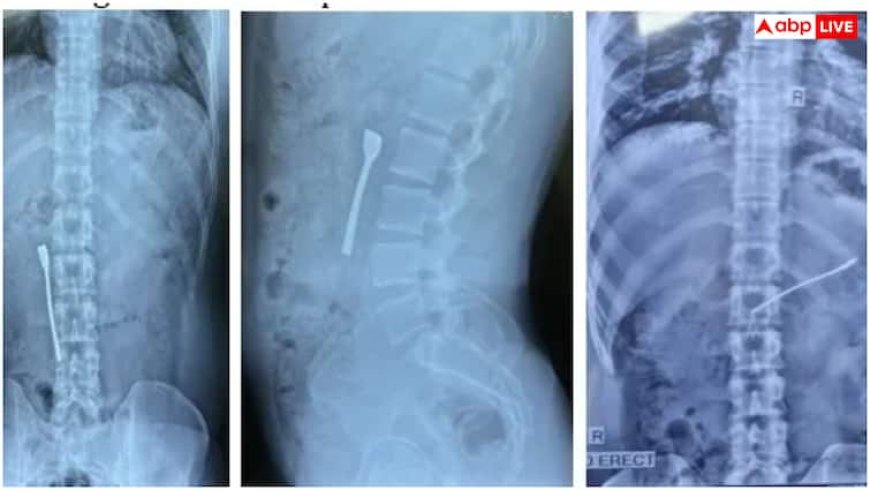

जून 2025 के दौरान दिल्ली के एक मल्टी-स्पेशियलिटी अस्पताल में 30 साल के युवक ने पेट में तेज दर्द और खाना न पचने की शिकायत की. उसने बताया कि दवाई लेते वक्त पानी के साथ स्टील का चम्मच उसने निगल लिया. यह चम्मच उसकी ऊपरी आंत में फंस गया था, जिससे उसे दिक्कत हो रही थी. डॉक्टरों जांच के दौरान देखा कि 8 सेमी की चम्मच मरीज की ऊपरी आंत में अटकी हुई है. यह बेहद खतरनाक कंडीशन थी, क्योंकि धातु की वस्तु आंत में छेद (पर्फोरेशन) या गंभीर इंफेक्शन का कारण बन सकती थी.

फोर्टिस अस्पताल के डॉक्टरों ने मरीज को एनेस्थीसिया देकर इमरजेंसी अपर गैस्ट्रोइंटेस्टाइनल (GI) एंडोस्कोपी की. इस प्रक्रिया में एक पतली लचीली ट्यूब एंडोस्कोप इस्तेमाल की गई. इस ट्यूब में एक कैमरा और लाइट लगी होती है, जो डॉक्टरों को इंटरनल ऑर्गन को देखने में मदद करती है. सर्जिकल टीम ने फोरसेप (स्पेशल मेडिकल औजार) की मदद से सावधानीपूर्वक चम्मच को आंत से निकाल लिया. चम्मच निकालने के दौरान मरीज की आंत को कोई नुकसान नहीं पहुंचा. महज 30 मिनट में पेट से चम्मच निकाल दी गई.